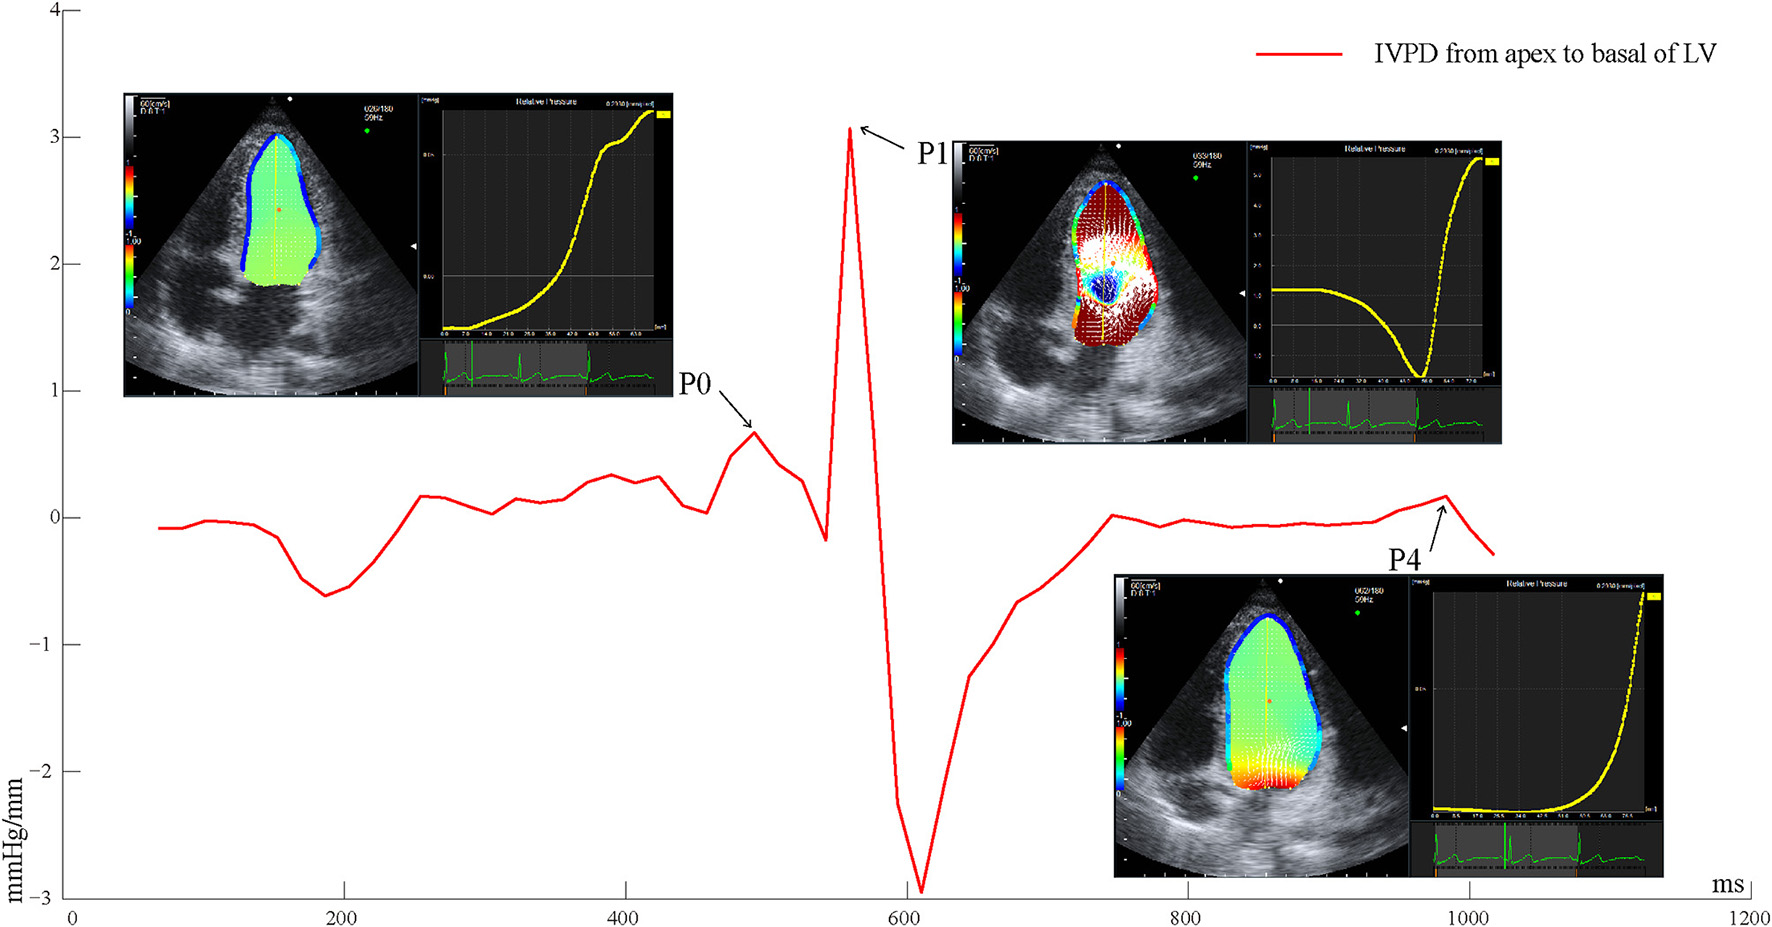

Echocardiographic images were captured over three successive beats, and color Doppler images in the apical four-chamber view were analyzed on the machine under the VFM configuration. Intraventricular flow velocity vectors of VFM were computed by solving the continuity equation using the flow velocity measurements obtained from color Doppler and the wall velocity measurements obtained from speckle-tracking echocardiography (5). The relative pressure imaging method was used to convert the velocity information into the relative pressure distribution using the momentum equations of fluid motion (Navier–Stokes equations) based on the VFM technology (Aloka, Hitachi Tokyo, Japan) (18). The endocardial border was manually traced at isovolumic relaxation and automatically determined throughout the remaining frames. By setting a sampling line from the apex to the base of the LV at isovolumic relaxation, a pressure difference between both ends of the line was calculated automatically for the whole cardiac cycle. The data of three cardiac cycles of the IVPD from the apex to the base of the LV were exported. The frame number of the peak value during isovolumic relaxation (P0), rapid filling (P1), and atrial systole (P4) was uniquely identified by simultaneously satisfying the following three conditions: (1) Valve opening and closing (P0 mitral and aortic valves closed; P1 and P4 mitral valve open, aortic valve closed), (2) Blood flow and direction (P0 blood flow was positively small and relatively static; P1 blood flow reached the first positive peak from the mitral valve to the apical direction; P4 had a positively small blood flow, and the blood flow was directed from the mitral valve to the apex of the LV), (3) The time-IVPD amplitude curve (as shown in Figure 1; P0 was the first small positive peak; P1 was the maximum positive peak value of the whole cardiac cycle; and P4 was the last positive peak during the diastolic period).

Figure 1

Time-IVPD curves of LV apical to basal of one cardiac cycle. LV, left ventricular; IVPD, intraventricular pressure difference; P0, isovolumic relaxation; P1, rapid filling; P4, atrial systole.

The peak values of the IVPD and IVPG (calculated by the IVPD divided by the length of the sample line) were extracted referring to the frame numbers of P0, P1, and P4. Differences in the peak IVPD between P0 and P1 (DiffP01), and between P1 and P4 (DiffP14) were calculated. The time intervals between P0 and P1 (P0P1), and between P1 and P4 (P1P4), were calculated by examining the frame differences between the peak IVPD of P0 and P1, and between the peak IVPD of P1 and P4, divided by the frame frequency. The peak rate of pressure decline was calculated through the steepest downward (negative) slope of the time–IVPD curve, reflecting the maximal decay in chamber pressure as the LV relaxed. All of the parameters were averaged over three consecutive cardiac cycles. The offline analyses of the IVPD parameters were processed with Matlab (MathWorks Inc., Natick, MA, USA).